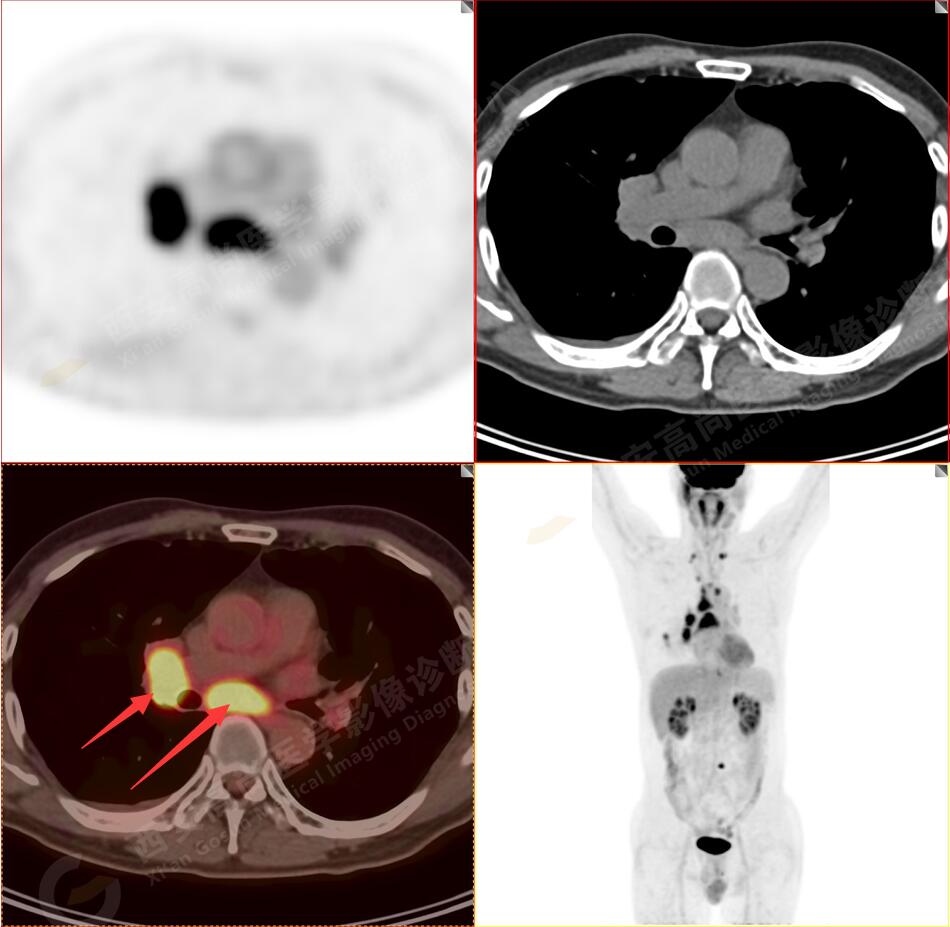

2.以下為全身多發(fā)轉(zhuǎn)移灶

3.右側(cè)肺門、縱隔(1L、1R、3A、4、6、7組)及雙側(cè)鎖骨上多發(fā)腫大淋巴結(jié),呈不同程度FDG代謝異常增高,考慮為淋巴結(jié)轉(zhuǎn)移。